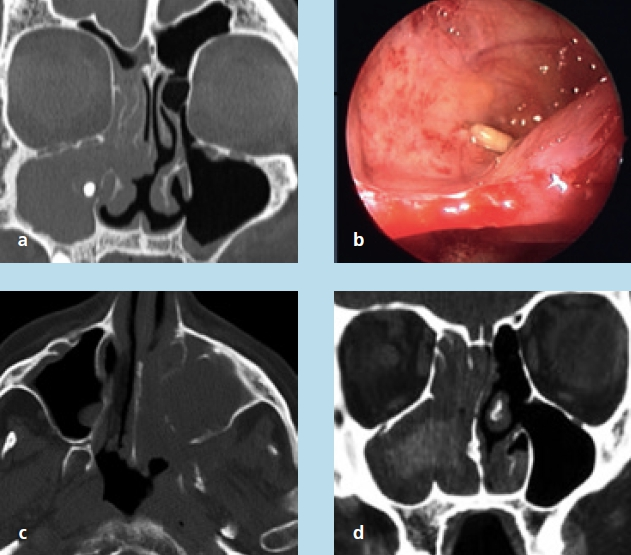

Eine kugelige homogene Verschattung in der Höhle wird im Rahmen der zahnmedizinischen und HNO-Behandlung häufig beobachtet (Abb. 5). Schmerz oder Druckgefühl werden in der Regel nicht angegeben. Bei diesen Retentionszysten handelt es sich oft um Zufallsbefunde, die bei bis zu 14% der Bevölkerung industrialisierter Länder gesehen wurden. Sie sind die Folge umschriebener intraepithelialer Sekretstörungen der Sinusschleimhaut und bedürfen im Falle klinischer Beschwerdefreiheit keiner Behandlung. Nur sehr große Zysten oder homogene Totalverschattungen sollten therapiert werden (Abb. 6). Häufig beklagen die Betroffenen ablaufende Nasensekrete mit unangenehmem Geruch und Geschmack. Im mittleren Nasengang sind endoskopisch eingedickte Sekretbefunde sichtbar (Abb. 7). Besondere Beachtung benötigen inhomogene Verschattungen mit gegebenenfalls sehr dichten Einschlüssen. Hier sind spezifische Infektionen (Pilzball), Tumoren oder Fremdkörper suspekt. Auch im Falle einer deutlichen Restbelüftung muss die Kieferhöhle exploriert und der Befund histologisch geklärt werden (Abb. 8a bis d).